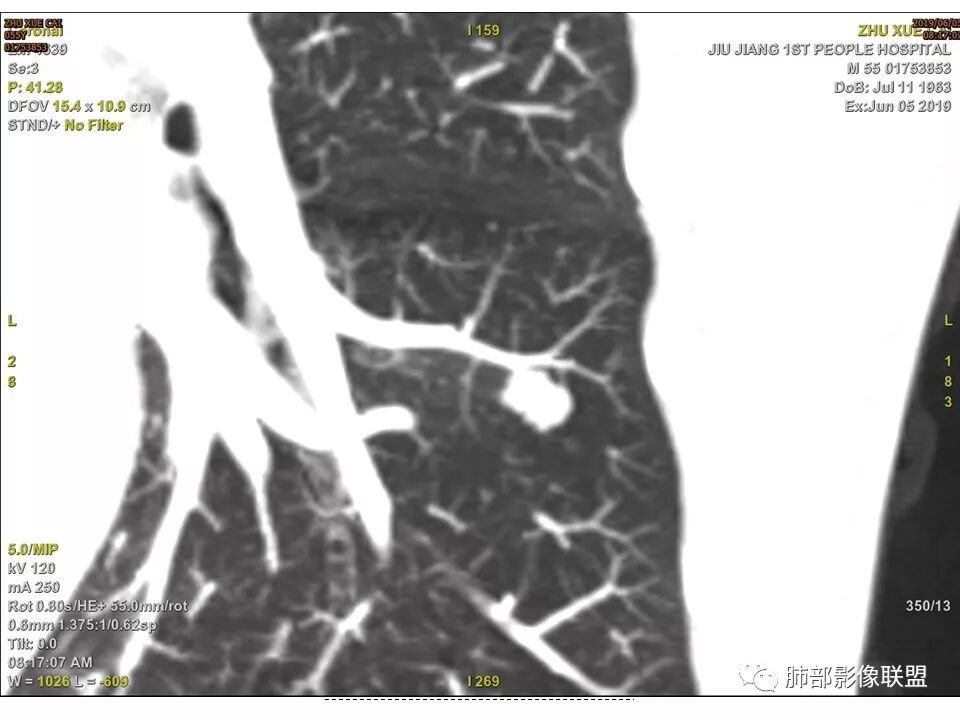

左肺下叶前内基底段结节 深分叶和脐凹 表面部分膨隆 部分收缩 支气管截断 轻度强化 中央有坏死 考虑鳞癌 鉴别炎性结节

病灶多结节融合,有分叶,也支气管截断,有细小血管连接,考虑恶性结节,周围型肺癌。

病灶部分平直丶内收,有脂肪密度,不强化支持错构瘤。部分病灶有结节堆积感,分叶,与支气管、肺动脉关系密切,需鉴别腺癌。不强化进一步结核结节。

左肺下叶前内基底段结节,轮廓凹凸不平,局部边缘平直,密度不均,近段支气管阻塞,增强前后CT值无明显变化,考虑肉芽肿,结核?腺癌代排

左肺下叶前基底段结节,病灶边缘分叶,边缘平直,u型征,可见气管截断,增强可见病灶边缘血管,平扫ct值低,轻度强化。考虑良性病变。

左下肺前内基底段结节灶,边缘分叶,相应支气管截断,增强后轻度强化,中央可见坏死。考虑麟癌。

典型CT特征包括:(1)圆形或椭圆形边界清楚的病灶。(2)大小1~4cm,有轻微分叶改变。(3)较均匀的软组织影,多伴有钙化。(4)无毛刺,卫星灶及肺门或纵隔淋巴结肿大。(5)CT增强扫描无强化或轻度强化,其强化可能与软骨瘤间质中的薄壁血管或周围慢性炎症反应有关。

鉴别诊断,主要是错构瘤。错构瘤是肺内最常见的良性肿瘤。错构瘤内常见“爆米花”样钙化,而软骨瘤钙化则多呈点状或环状钙化。病灶内脂肪密度影是错构瘤的特异性征象,而软骨瘤内无脂肪成分。此外尚需要与肉芽肿性炎、硬化性肺细胞瘤、肺癌、转移等鉴别。